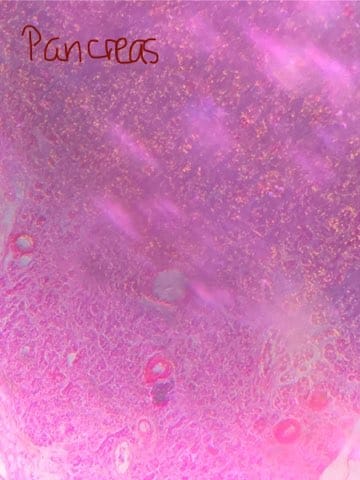

Identify this slide.

Pancreas